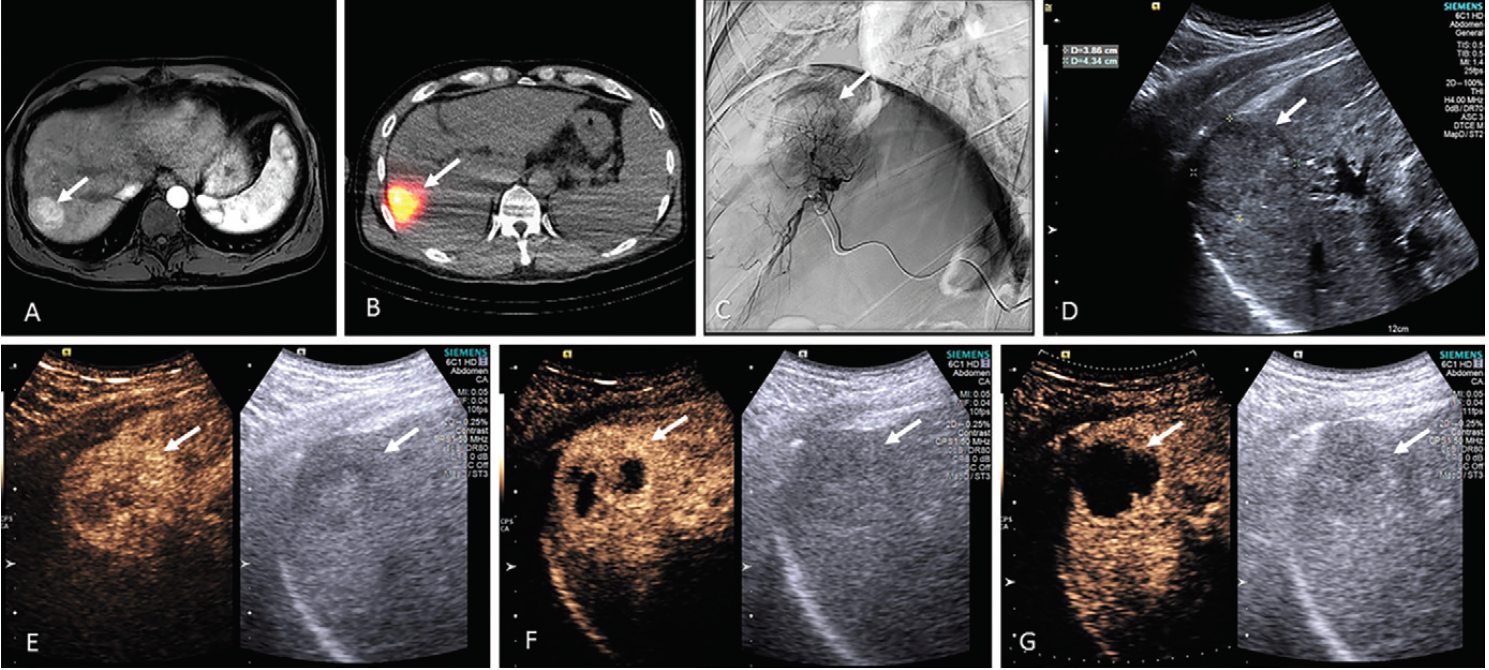

CEUS is a safer, less expensive option for diagnosing focal liver disease.